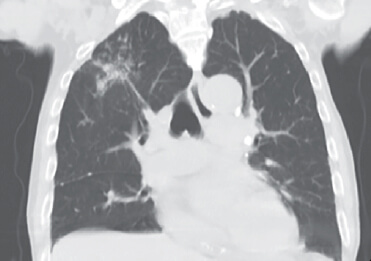

Figura 1

Figura 2

Figura 3

En la radiografía de tórax se observó una sombra en el campo superior del pulmón derecho (Figura 1). La tomografía computarizada de tórax reveló nódulos con opacidad de vidrio esmerilado en el campo superior del pulmón derecho (Figuras 2 y 3). No tenía antecedentes de tabaquismo y trastornos respiratorios.

La respuesta es D: tuberculosis pulmonar. Se